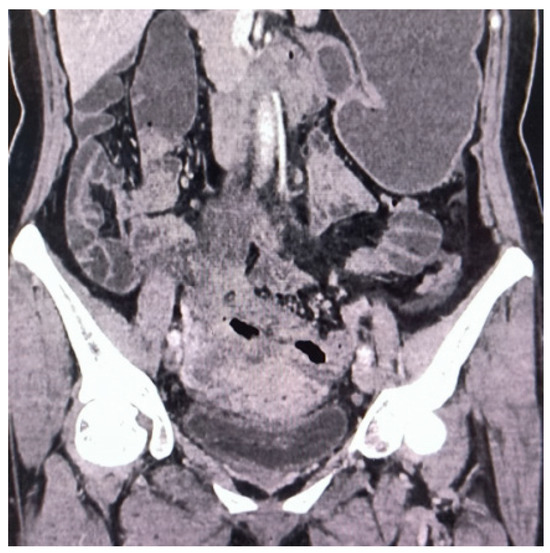

Figure 1. Contrast-enhanced computed tomography (CT) revealed roughening and thickening of the sigmoid colon and upper rectum walls, with luminal narrowing and uneven enhancement. In conjunction with laboratory examination (RBC 2.95 × 1012/L, Hb 80 g/L, WBC 12.3 × 109/L, CRP 53.44 mg/L, CEA 1.73 ng/mL, AFP3.64 ng/mL, CA125 19.2 U/mL, CA19-9 8.83 U/mL), CT indicated possible inflammatory lesions with pelvic lymph node enlargement.

Diagnostics 14 01923 g001